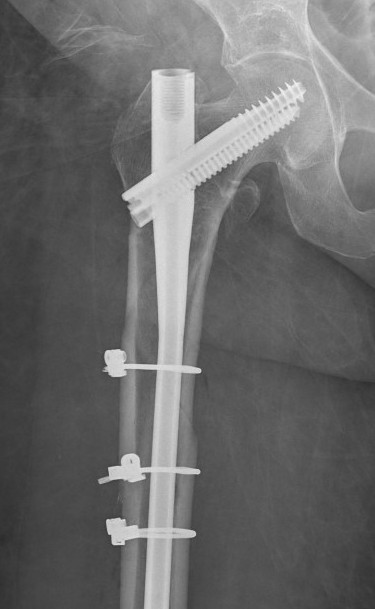

B. Cephalomedullary nails

- gold standard

- load sharing or load bearing, dependant on reduction

Piriformis reconstruction Gamma nail TFNA with helical screw Intertan nail

Technique IMN

Entry point

Greater trochanteric

- simple

- need proximal fragment reduced

Piriformis

- may aid reduction, as a trochanteric nail will push proximal fragment into valgus

- more difficult to obtain